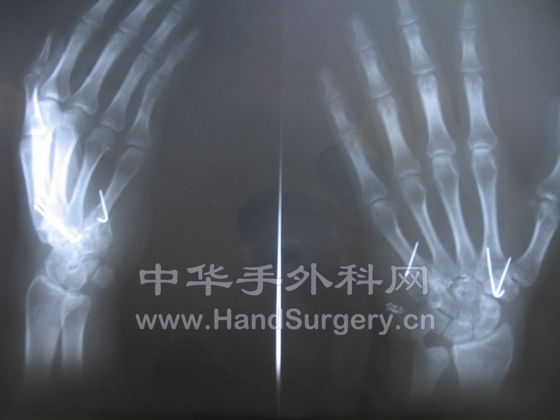

最近做一例断腕,多指教

断面怎么整齐的腕部离断,成活我想问题应该不大,还有看图片腕骨应该是直接内固定吧!只是不知道目前功能怎么样

术中正位X光片,不好意思,小了点

此处离断成活不是多大问题,关键是功能恢复的好坏,以及术中骨的处理。

近排腕骨有没有去掉?屈伸功能展示的不完全